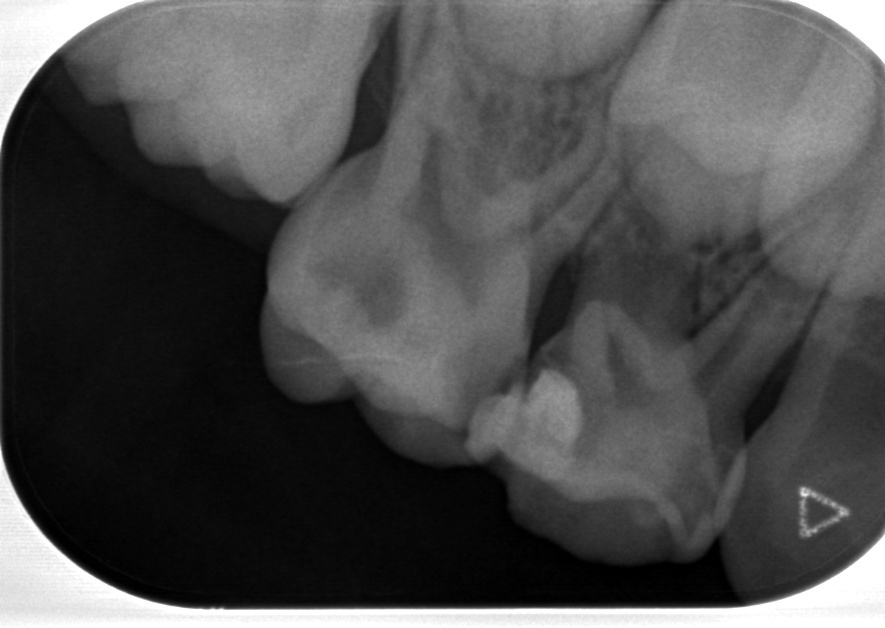

下記のレントゲン写真のようにう蝕(虫歯)が歯の歯髄(神経)とかなり近接して

いる場合でも無症状だったりします。

大人であれば神経にこのぐらい近接している虫歯であれば冷たいものがしみたり

食事の時に痛みが出たりします。